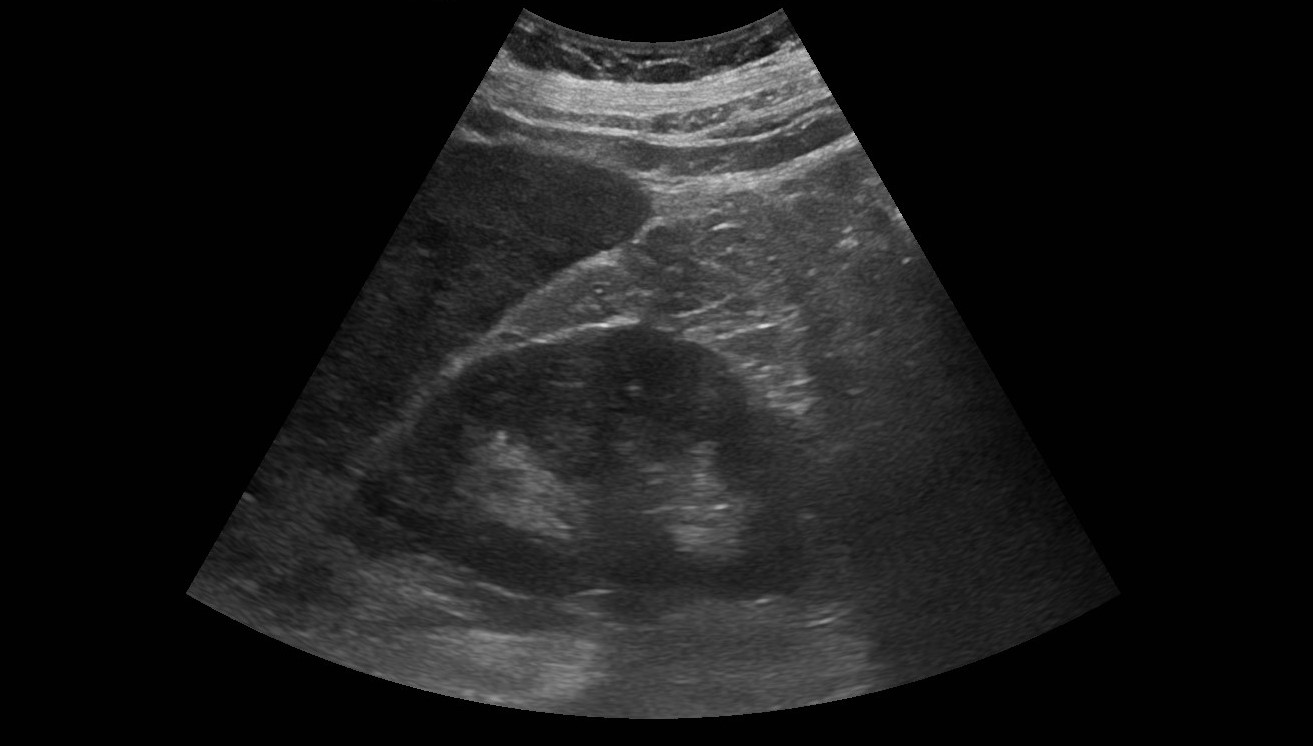

Se realiza analítica con perfil hepático: GOT 100, GPT 55, GGT 454 y FA 218 con proteína C Reactiva 146 y Lactato deshidrogenasa 1.227; por lo que se realiza ecografía clínica a pie de cama con hallazgo de múltiples imágenes hipoecoicas en parénquima hepático.

Se cursó ingreso ante el diagnóstico del paciente con posterior estudio de las imágenes hepáticas con resultado de neoplasia pancreática con incontables metástasis hepáticas.